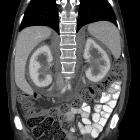

- kidneys and retroperitoneum

- often involved

- usually asymptomatic

- hairy kidney sign: irregular symmetric infiltration of the bilateral perirenal and posterior pararenal spaces

- coated aorta sign: periaortic soft tissue

- inferior vena cava and pelvic ureters are typically spared, which are useful cross-sectional imaging findings for differentiation of retroperitoneal Erdheim-Chester disease from retroperitoneal fibrosis